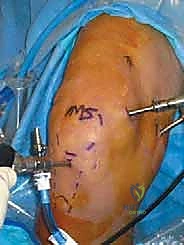

We begin by marking our portals on the skin. A complete synovectomy typically requires five or six portals to ensure thorough access to all compartments.

Observe the typical portal markings on this right knee. Accuracy here is crucial for optimal visualization and instrument maneuverability.